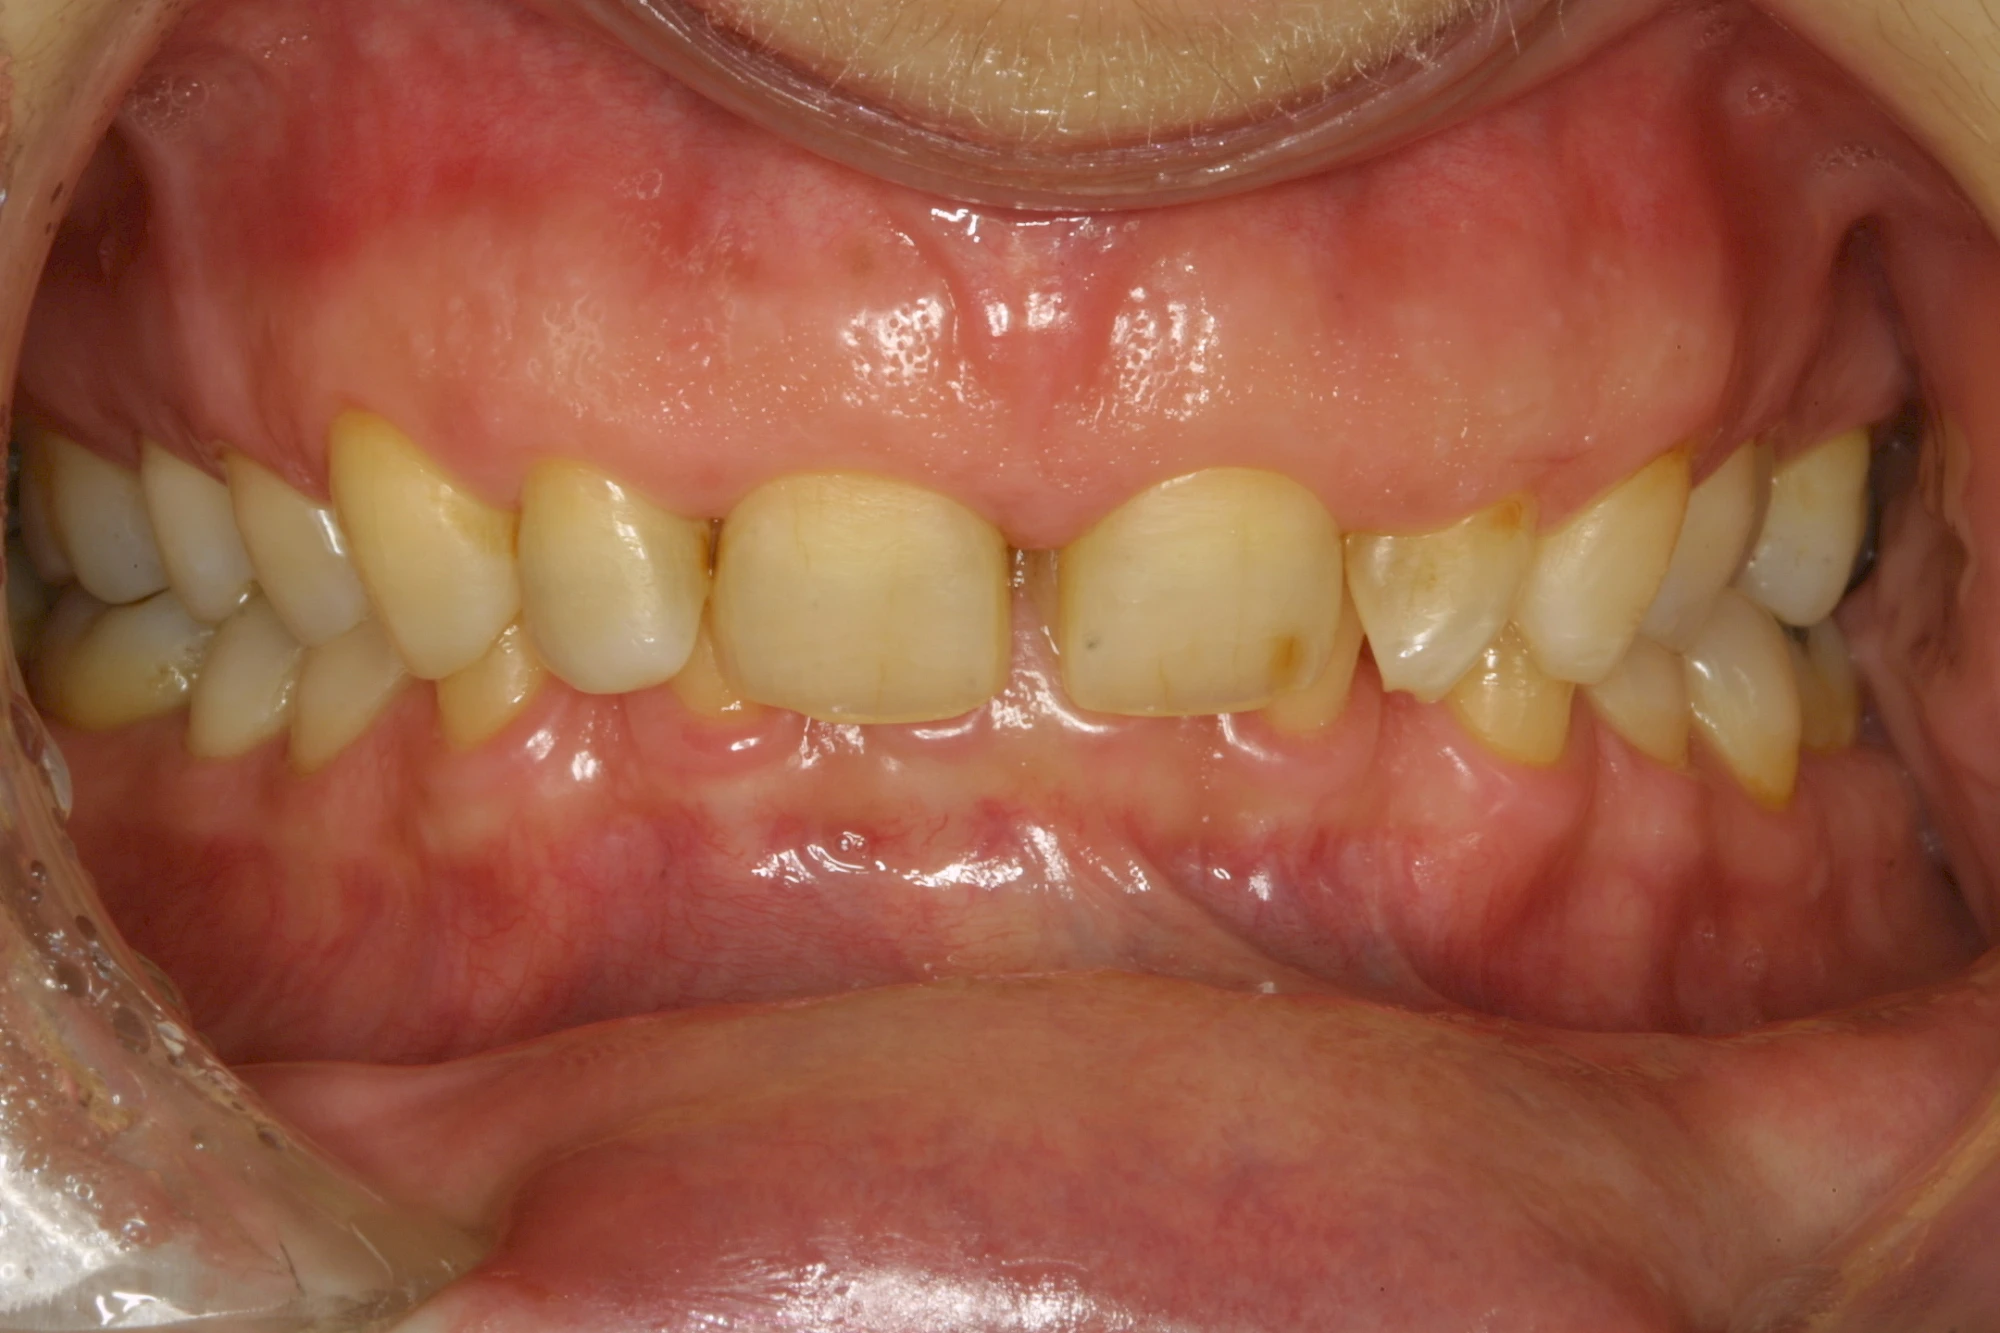

Über die Zeit können verschiedene Prozesse die Zahnhartsubstanzen aufzehren:

- Abnutzung durch Kauen (Abrasion) oder duch durch übermäßiges Knirschen bzw. Pressen (Attrition)

- Säurebedingte Auswaschung (Erosion)

Auswaschung (Erosion) dagegen ist eine Verschleißerscheinung der Zähne aufgrund von immer wiederkehrenden Säureangriffen durch die Nahrung, verstärkt zum Beispiel durch den Genuss säurehaltiger Getränke oder Speisen. Auch bei Menschen mit einer Essstörung (z. B. Bulimie) können die Zähne durch die Magensäure ausgewaschen erscheinen.